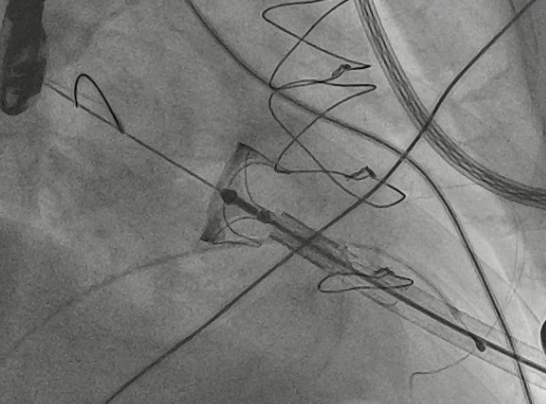

收缩期未见瓣周漏

左房内未见对比剂显影